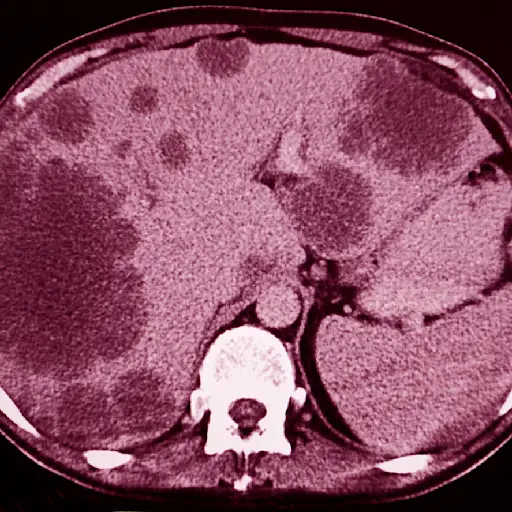

肝脏中的转移可能不会引起症状

你可能不是第一个注意如果乳腺癌会扩散到肝脏;根据breastcancer.org网站的说法,通常情况下,没有任何征兆。

肝功能测试可以检测出血液中酶和蛋白质的异常水平,这可能表明癌症已经扩散到肝脏。

肝脏转移的迹象

当肝脏转移确实会导致症状时,它们可以包括:

- 腹痛或不适;恶心

- 极端疲劳;弱点

- 减肥;食欲不振

- 发烧

- 腹胀

- 腿部,脚和手肿胀

- 皮肤变黄或眼睛的白人

- 皮肤发痒或起皮疹